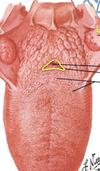

opening of auditory tube

Pharyngeal Recess

Genioglossus Muscle

epiglottis

the ventricle

above the ventricle

false vocal cords

true vocal cords

levator palati muscle

Tensor Palati Muscle

uvula

Palatoglossal Fold or Arch

Palatopharyngeal Fold or Arch

tonsilar bed

vestibular folds

true vocal cords

epiglottis

piriform recess

soft palate